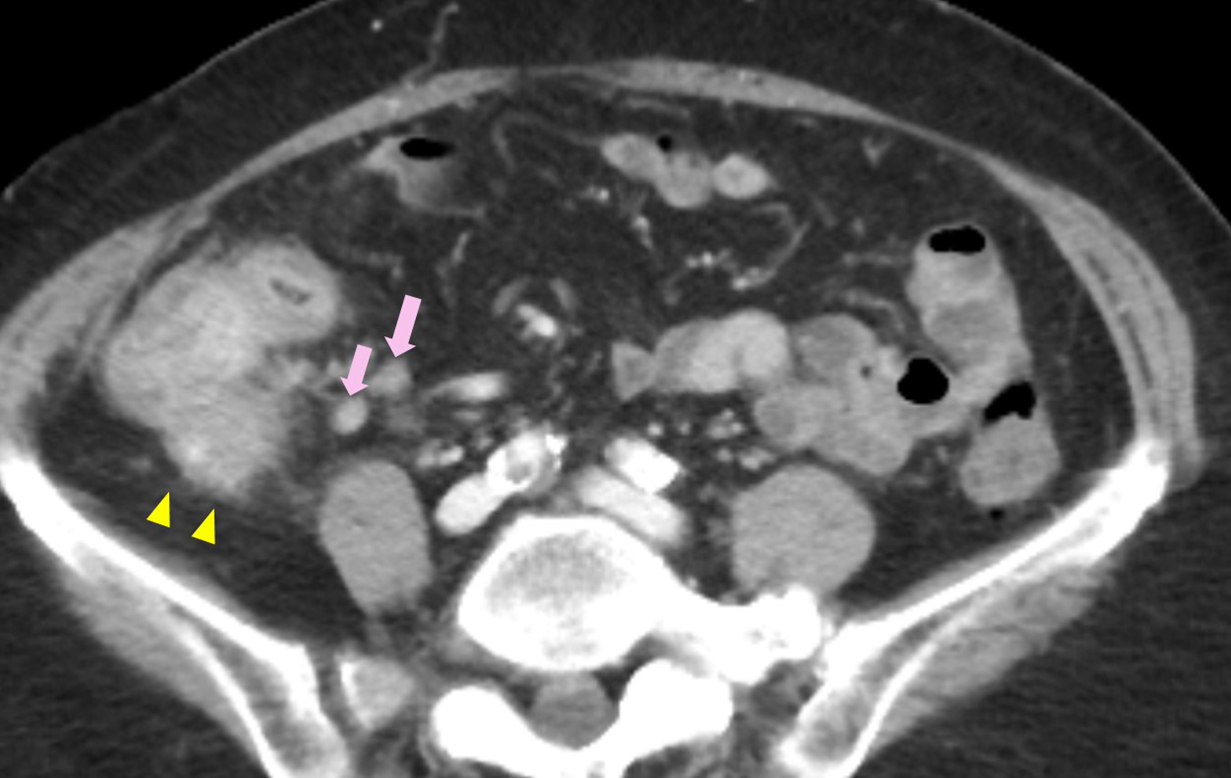

腹部CT所見:虫垂の腫大,および虫垂から盲腸にかけて造影効果を伴う不整な壁肥厚を認めた.腹水はなく,播種結節や遠隔転移を疑う病変はみられなかったが,回盲部リンパ節の軽度腫大を認めた(Fig. 1).

Abdominal CT showed the thickening of the wall of the ileocecum (arrows) and enlarged lymph nodes (triangles).